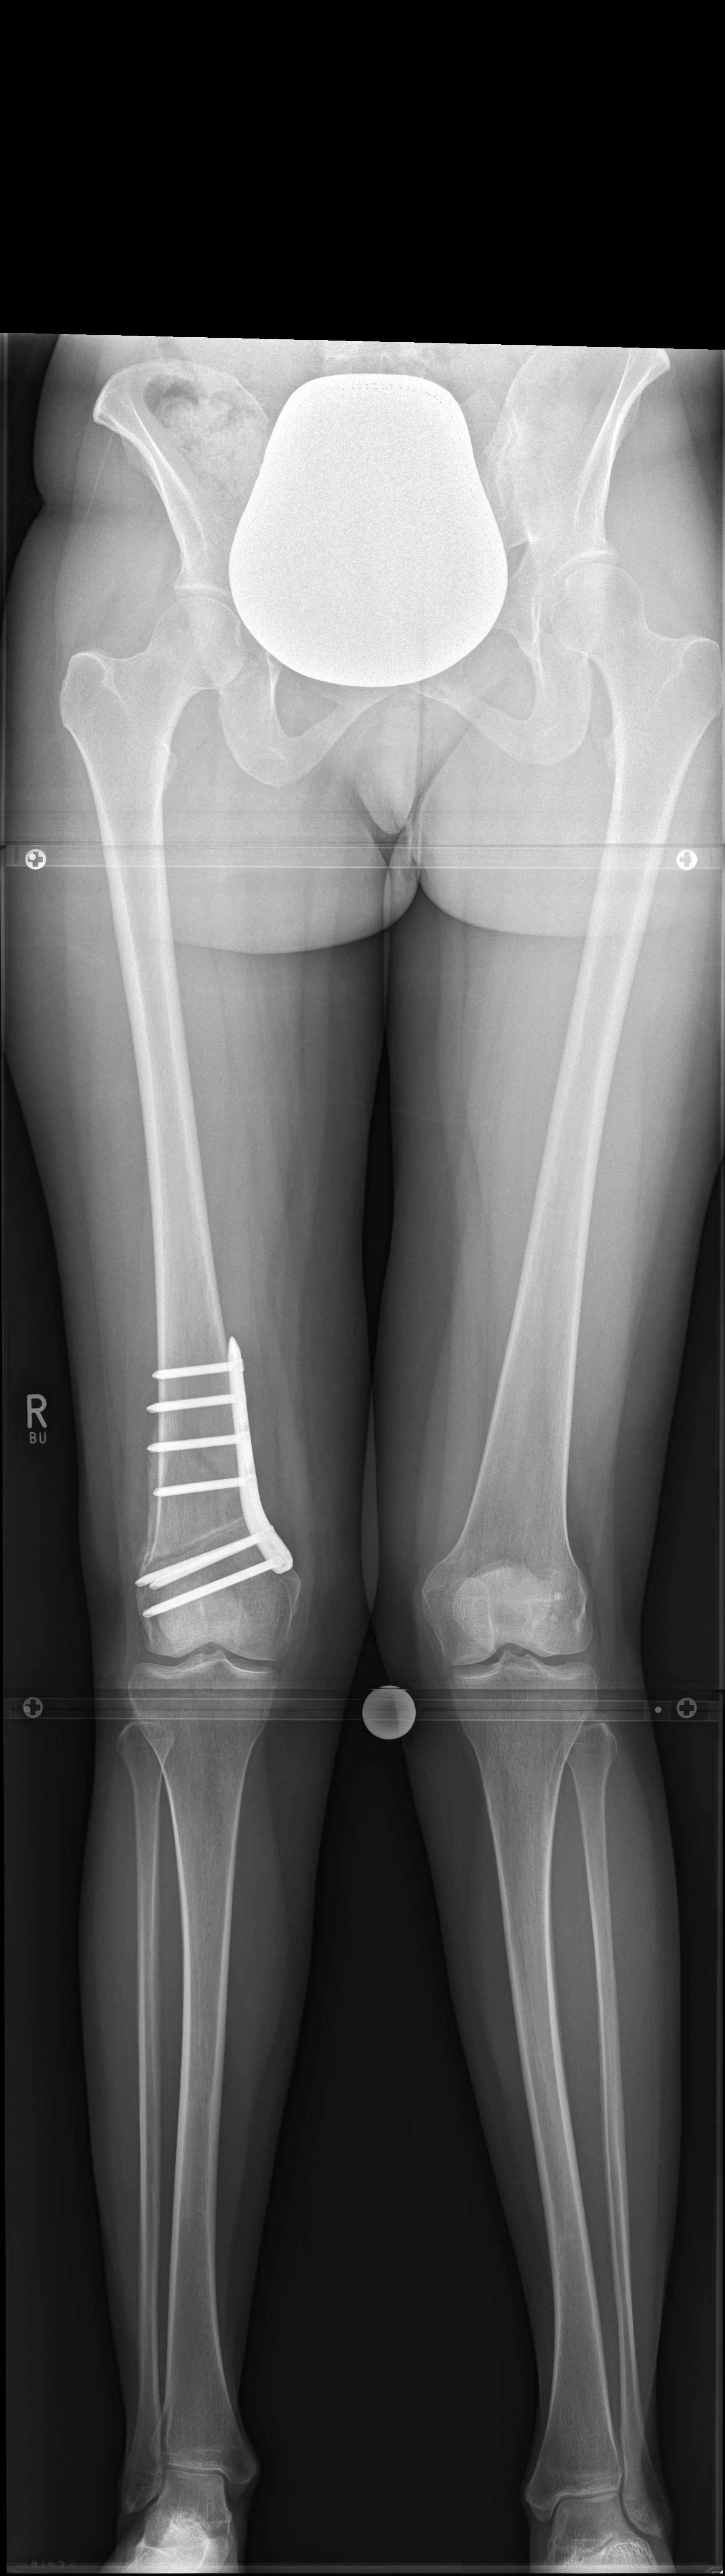

Case 2

(Case provided by Steffen Schröter)

A 52-year-old man with a posttraumatic deformity 2 years after tibial plateau fracture AO/OTA 41C3.3e, PL, PM complained of pain after a normal working day. The patient was a heavy smoker. Activities like sports or hiking were discontinued. Surprisingly ligaments in the coronal and sagittal planes were stable. There was no effusion. Pain was localized in the medial compartment. The range of motion was limited to 0/0/130°. The deformity was corrected with a high tibial osteotomy.

Showcasing a high tibial osteotomy case